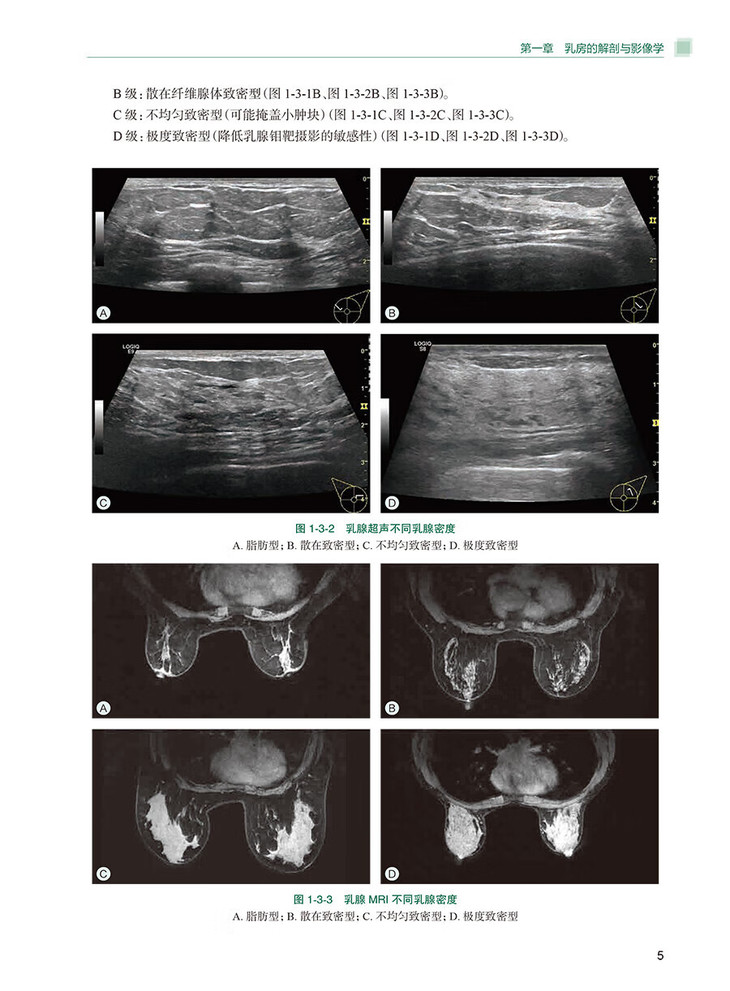

第三节乳腺的密度与分级/4